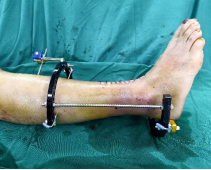

1.CO外固定半環(huán)連接跟骨穿針并通過CO接骨機器人配套的連接桿與CO接骨器人中間機械臂相連,調(diào)整機械臂,進(jìn)行骨折端初步復(fù)位,C臂確認(rèn)復(fù)位滿意,關(guān)節(jié)間隙拉開。

連接CO接骨機器人

牽拉復(fù)位